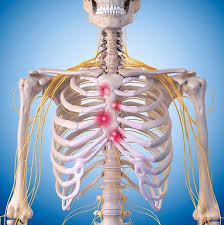

1. 해부학적 위치 이해하기

- 왼쪽 가슴 위쪽은 흉골 왼쪽과 늑간(갈비 사이), 어깨뼈 아래 부위까지 포함됩니다.

- 심장·폐·식도·위장이 이 부위를 공유하고, 흉벽(늑연골, 근육)도 통증의 주요 원인이 될 수 있습니다.

- 중요한 건, 통증이 위치만으로 진단될 수 없다는 점입니다. 기침·호흡·운동 등 상황에 따라 원인이 달라집니다 :contentReference[oaicite:1]{index=1}.